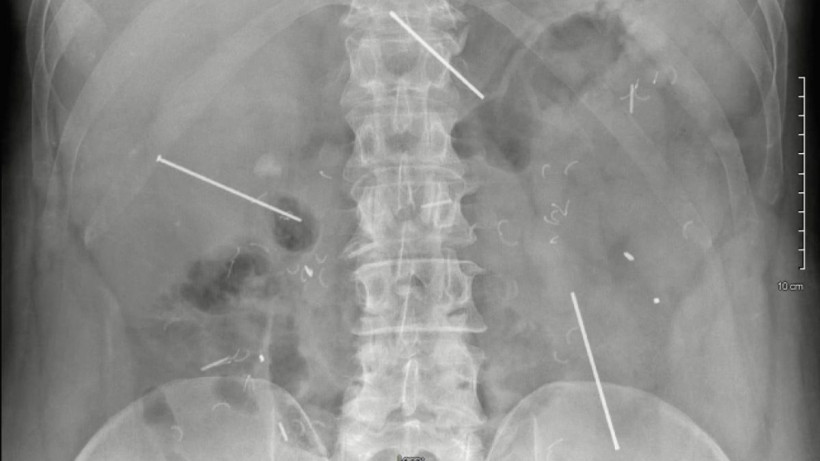

© Ahmed A E, Lopez Hanson R J, et al., Cureus

Фото: © Ahmed A E, Lopez Hanson R J, et al., Cureus

Первичный осмотр не выявил серьёзных отклонений, но рентген и КТ-обследование показали наличие трёх металлических предметов в брюшной полости. Один гвоздь прошёл через левую долю печени и поджелудочную железу, второй — через правую долю печени, а третий застрял между петлями тонкого кишечника.